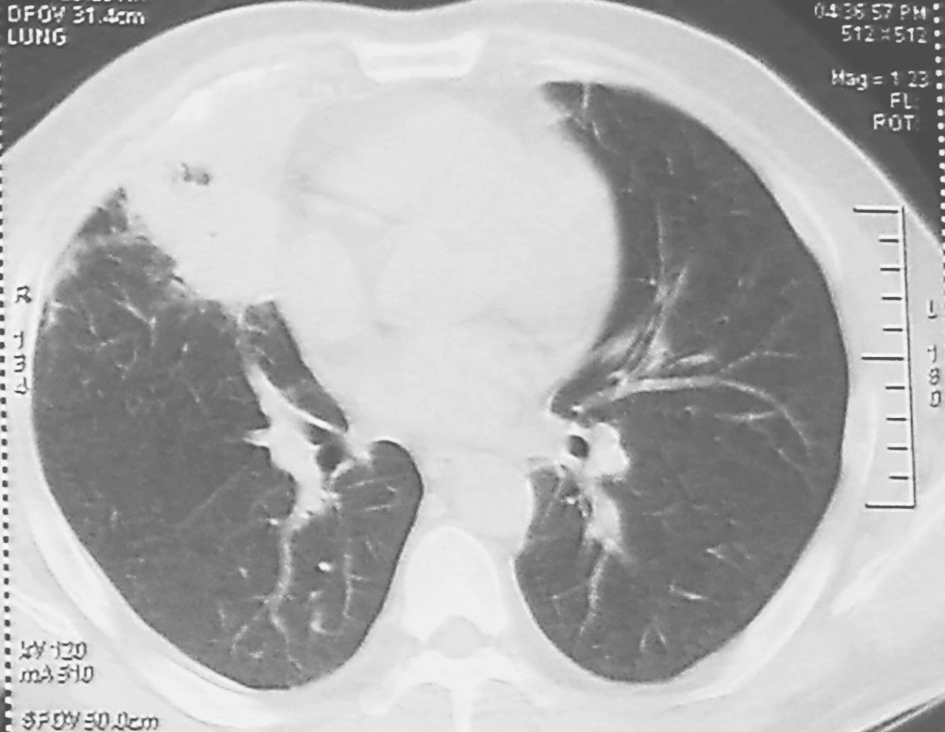

图1 胸部CT表现(2011-01-05)

胸部CT可见右肺中叶实变